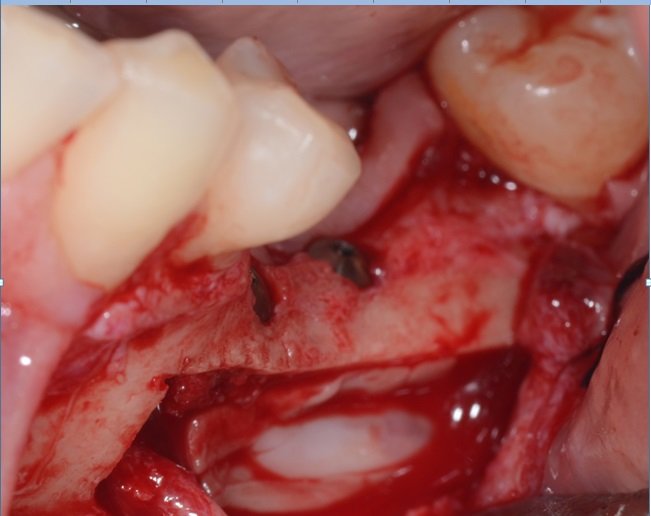

Remoção do osso vestibular com um cinzel curvo para ter acesso ao nervo alveolar (Fig 7).

Osteotomia óssea ao redor do foramen mentoniano para liberação total do nervo.

Depois da remoção do bloco ósseo retiramos o osso medular com curetas de Lucas ou molt até a completa visualização do nervo alveolar.

Colocação do guia cirúrgico e marcação do local ideal dos implantes.

Descolamento do nervo alveolar, deixando-o solto dentro do canal. Podemos colocar um túnel check ou fresa deslocando o nervo para o lado em um dos alvéolos artificiais enquanto terminamos a fresagem e colocamos os implantes.